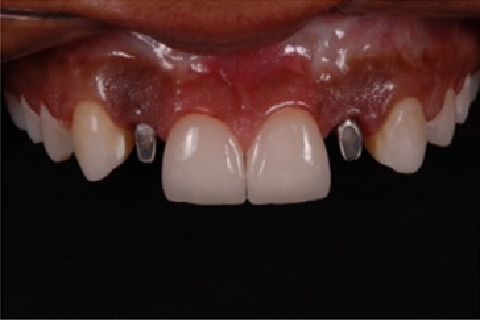

''Neste caso, a paciente gostaria de melhorar a estética do seu sorriso, prejudicada pela agenesia de ambos os incisivos laterais superiores. Devido à baixa disponibilidade óssea, observada na tomografia computadorizada, optou-se pela instalação de implantes estreitos (Xive – Dentsply Implants – 3.0 mm de diâmetro) com regeneração simultânea (Biooss e Biogide – Geistlich), ao invés de realizar enxerto ósseo prévio. Após osseointegração, foi realizado condicionamento gengival com provisórios e novo enceramento diagnóstico. O caso foi finalizado com coroas livres de metal sobre os implantes e microlaminados cerâmicos sobre os incisivos centrais (e.max - dissilicato de lítio – Ivoclar Vivadent), visando o mínimo desgaste de estrutura dental sadia. ''